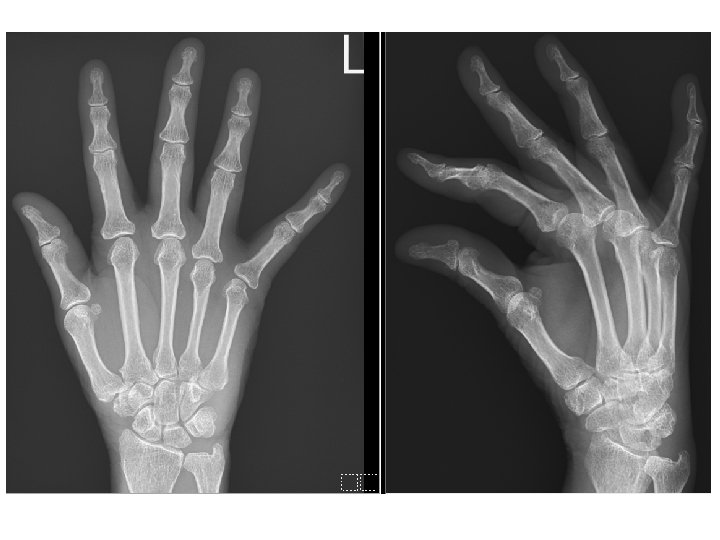

Hospital course (AIR survey) l Immune profile: ANA: 1: 640 H, anti. SSA>240, anti-SSB(-), RF(-), ACPA(-), C 3: 16. 6, C 4: 4. 8, Ig. G: 2010, Ig. A: 480, Ig. M: 43. 4, Ig. E: 14. 1 l HSCRP: 3. 73, ESR: 15 mm/hr

Problem list Chronic lower abdominal pain l Poor appetite + body weight loss l Ascites => Serositis or nephrotic l Polyarthralgia, sicca complex => Suspect Sjogren’s syndrome, D/D: SLE l Others: nausea/vomiting, DOE, microcytic anemia, CBD dilatation l Confirmed: GERD and gastric ulcer, C. difficile associated diarrhea, nephrolithiasis l